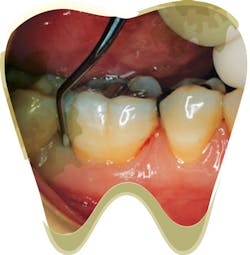

Recognizing burnished calculus can be challenging, even for the skilled clinician. Isolated areas of tissue color change, slight inflammation, or bleeding upon probing in a patient who effectively brushes and flosses regularly may be signs of areas where burnished calculus is present. These areas will not heal until the irritant is removed. Change the way you examine your patient to determine if burnished deposits are present.

- Carefully view the color and consistency of the gingival tissues, paying close attention to interproximal areas and line angles (where the tooth curves and you need to pivot on your fulcrum while rolling your instrument to adapt). Look for red or blue shades as well as swelling. The body’s first line of defense from any foreign object is to send in the white blood cells to cause tissue to become angry red and inflamed.

- Use a generous amount of air and blow toward the cervical tissue at a 45-degree angle. Allow the tissue to distend while you view the sulcus. Many times, I have noticed undetected burnished deposits when I’m using the air polishing unit. Try polishing prior to scaling in an effort to support the newest clinical success while locating burnished calculus at the same time.

- Pick up your posterior explorer (11/12) and gently search for irregularities. Lighten up your grasp as if you were holding a fragile piece of china. Feel for the slightest elevation. You will not feel a deposit that “clicks”; burnished calculus will be a smooth, raised bump.